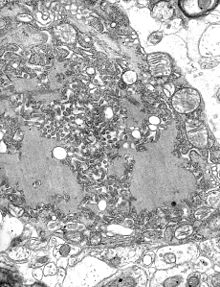

Hsv encephalitis.jpg

MRI scan image shows high signal in the temporal lobes and right inferior frontal gyrus in someone with HSV encephalitis.